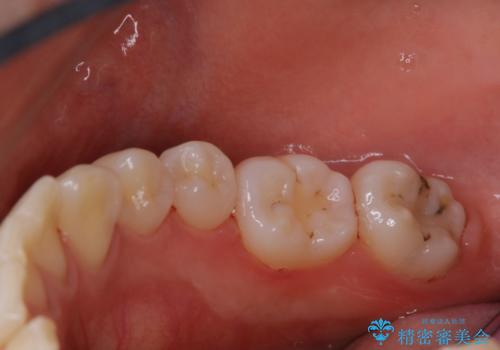

磨きにくい奥歯の歯磨き指導とPMTC

- 奥歯の磨き方が難しく、上手く歯磨きできないためクリーニングで除去して欲しいとのことでした。PMTC30分コースを行い、歯磨き指導も行いました。

染め出しを行い、どこに歯ブラシが当たっていないか確認し、ブラッシングの改善ができるように指導も行いました。